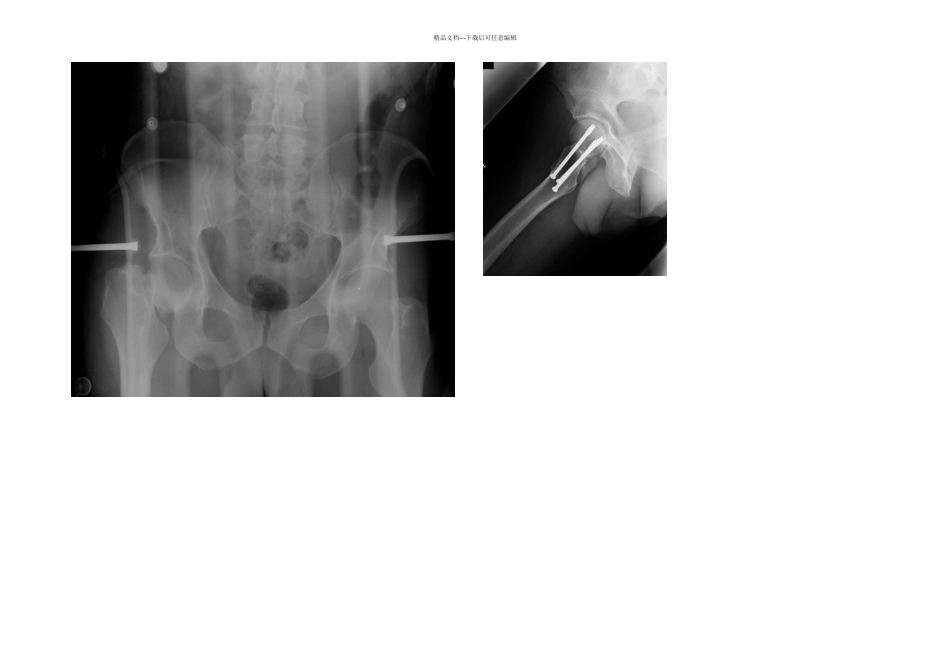

精品文档---下载后可任意编辑2024-11-12 11:39 来源:丁香园作者:紫川秀第二 童勇骏字体大小-|+[ 编者按 ]: 股骨颈骨折在骨科临床工作中并不少见,以老年患者多见,而年轻患者少见,人群分布特点符合疾病进展趋势。现阶段股骨颈骨折的治疗,即便是在老年人群中也有较多争议,对年轻患者更是如此。丁香园骨科板块内讨论年轻股骨颈骨折的治疗帖子也较多,在帖子学习中发现了这一篇发表在 2024 年 JBJS 上的文章,论述了年轻患者股骨颈骨折的相关问题,虽然时间过去 6 年多,很多观点在改变,但是其中一些内容看看还是很有启发性。 股骨关节囊内型的股骨颈骨折在老年人群中较为常见,通常在轻微外伤后即可引发。在正常的年轻人群中较为少见。年轻的股骨颈骨折患者,通常合并的内科疾病较少,活动量多,骨头质量好。对年轻和老年患者股骨颈骨折的不同特点认知有助与制定合理的治疗方案。年轻患者的股骨颈骨折并发股骨头坏死的几率很高,文献报告在 12%-86% 之间。该并发症会导致股骨头塌陷和髋关节骨关节炎。保留髋关节的挽救性手术,如股骨截骨术等失败率较高,而髋关节置换术对年轻,高活动量的患者则并非一个最好的选择。除骨折解剖复位和坚强固定对股骨颈骨折的预后有重要影响之外,其他多个因素,如手术时间,关节囊切开术,固定的方法等年轻患者股骨颈骨折的最终影响仍有较大争议。下面的知识有助于临床医生对年轻患者股骨颈骨折治疗认识的进一步深化。解剖股骨头血供主要来源于 3 个动脉:旋股内侧动脉,旋股外侧动脉,闭孔动脉。在成人中,闭孔动脉通过股骨头园韧带为股骨头提供的血供,量较少,并且变化也较大。旋股外侧动脉通过升支形成股骨干动脉,供应股骨头前下方大部分血运。旋股内侧动脉供应股骨头大部分血运,特别是股骨头外上方。股骨干骺端外侧动脉来源于旋股内侧动脉,并沿着股骨头的后上侧横行,进入股骨头。上述终末端供应股骨头血供的血管均在关节囊内;因此,股骨头骨折后骨折移位可以造成上述终末血管的断裂,从而导致股骨头坏死。股骨头坏死相关的因素包括,股骨颈骨折初期造成的股骨头血管损伤,骨折复位的质量,股骨关节囊内压力等。诊断在老年人群中,股骨颈骨折通常由轻微暴力所致。老年患者骨头质量较差,内科合并症较多,有摔倒倾向等均是容易发生股骨颈骨折的危险因素。对年轻人群来说,股骨颈骨折的原因通常是高强度的暴力,如摩托车撞击,或者从较高处坠落。这类患者受伤机制是,下肢在外展位时遭...